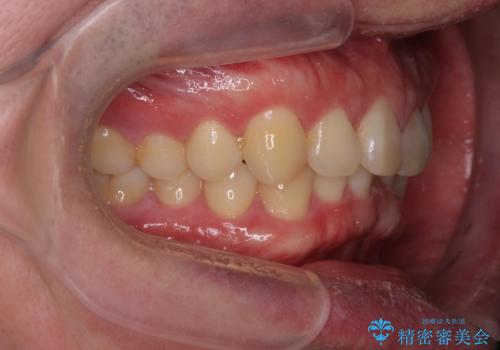

下の歯のがたつきが気になる。 インビザラン&ワイヤー部分矯正併用

- 下の歯が気になるとの事で来院。

左上の奥歯がシザーバイトがありワイヤーで部分的な矯正を行い、シザーバイトを改善した後にインビザラインで全体的な矯正治療を行いました。

歯のがたつきが改善され大変満足されました。